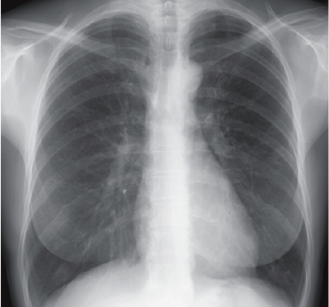

正常な肺